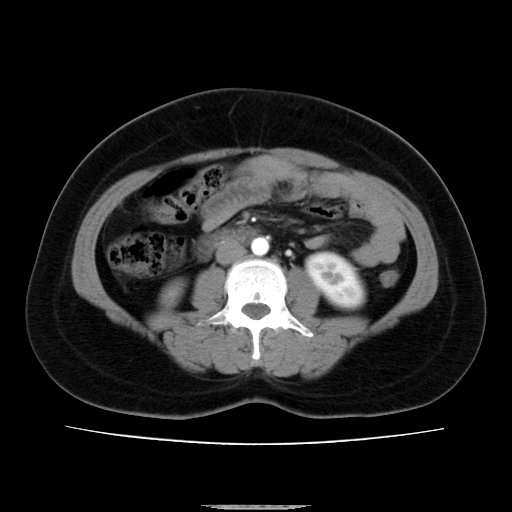

标题: CT14225:女性46岁。当地B超示肝内占位,来我院作CT检查。请 [打印本页]

标题: CT14225:女性46岁。当地B超示肝内占位,来我院作CT检查。请

速升速降,支持肝癌.脾体积增大,形态欠规整,请询问病史是否做过脾动脉栓塞.

右叶肝癌灶;慢性胆囊炎,不除外占位;;副脾可能性

肝内结节强化特点符合原发性肝癌表现,脾脏改变考虑为增大及先天发育所致。

符合肝癌表现,脾脏大(肝硬化?)

非常典型,肝ca,脾脏先天性发育异常,脾大

肝内结节强化特点符合原发性肝癌表现。脾大。